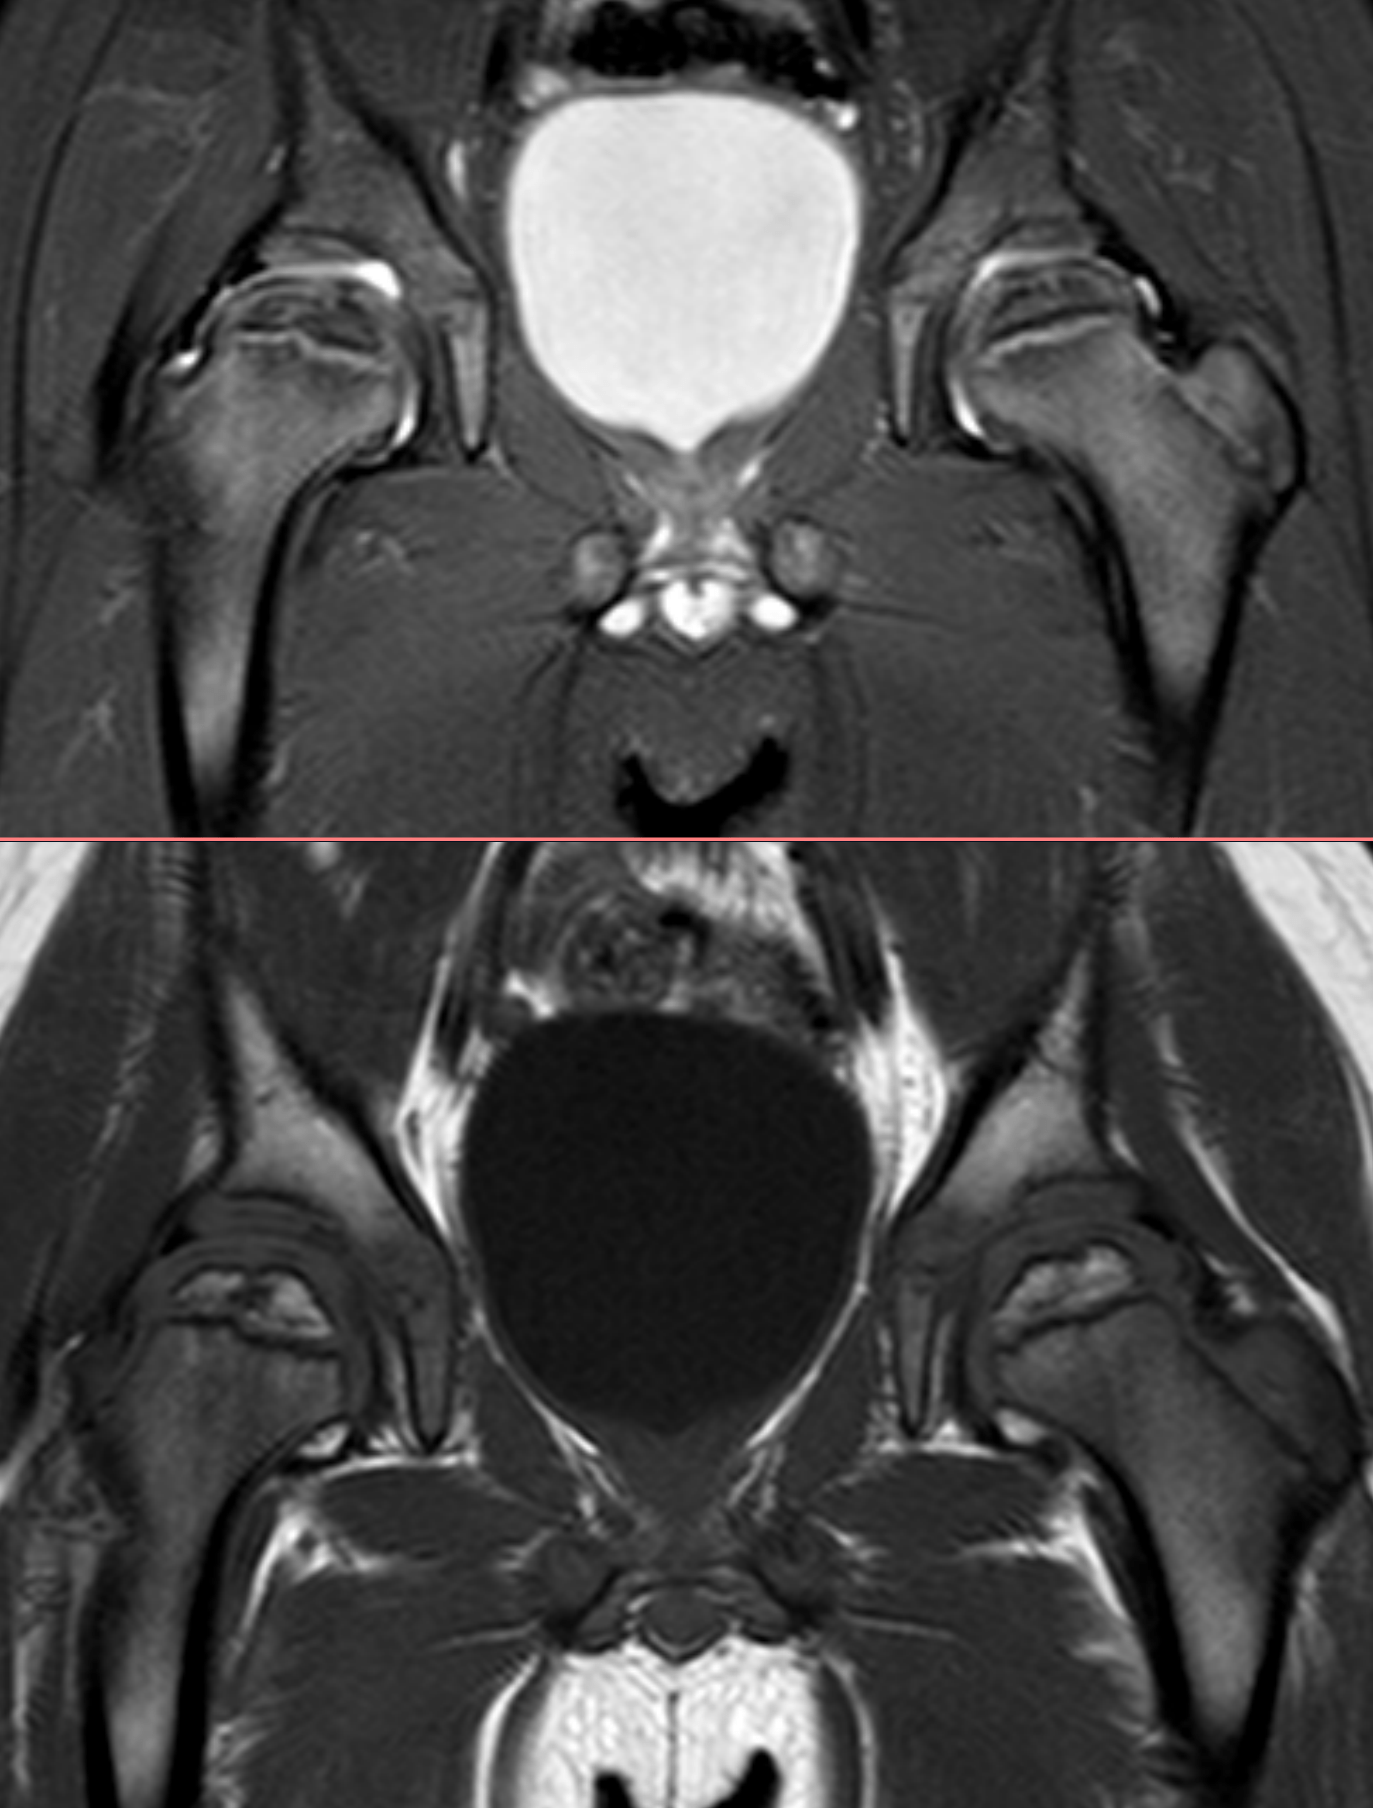

4y, male, pain

Pain in the right leg.

Bilateral Legg-Calvé-Perthes disease or bilateral Meyer dysplasia?